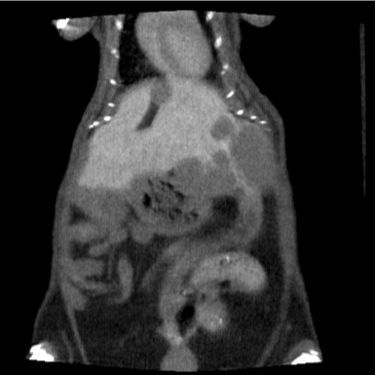

Sample microCT images (vasculature of a mouse brain, partially filled with barium sulfate - 11 micron pixel size; liver tumor visualized with IV iodinated contrast agent)